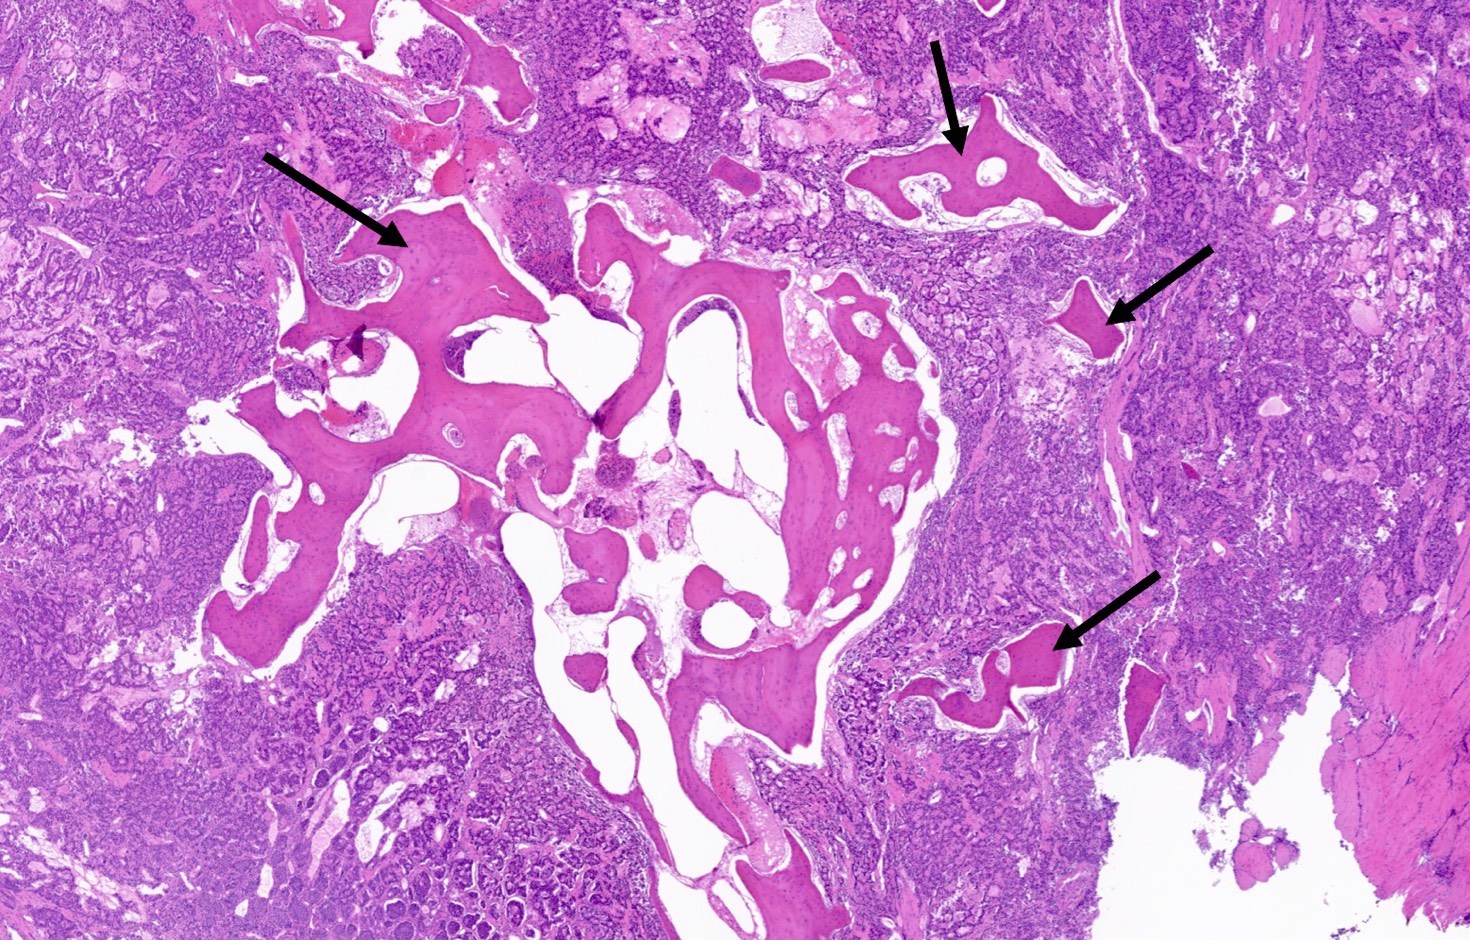

Microscopic (histologic) description

- Diagnostic criteria

- Neuroendocrine tumor with size ≥ 5 mm with < 2 mitoses/2 mm2 and absence of necrosis

- Neuroendocrine growth pattern (organoid, trabecular, rosette formation, nested) or pseudoglandular, follicular and papillary growth

- Stroma is fine and highly vascularized; hyalinization, cartilage or bone formation are possible

Microscopic (histologic) images

Contributed by Philippe Joubert, M.D., Ph.D., Jijgee Munkhdelger, M.D., Ph.D. and Andrey Bychkov, M.D., Ph.D.